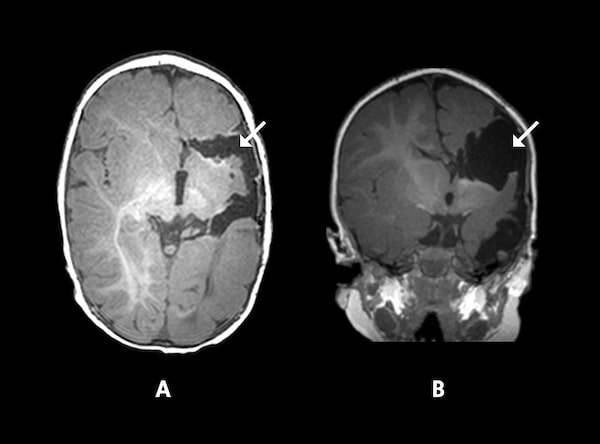

MRIs for a two-and-a-half-old patient of Dr. Rutka where top (A) and side (B) views show minimal brain tissue removed during a functional hemispherectomy.The Hospital for Sick Children/Supplied

Since 1987, Dr. Rutka and his colleagues at SickKids have done hemispherectomies on at least 28 children with HME. But what kind of future can a child have when half of their brain goes dark?